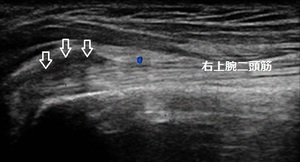

右肩前面(患部) 左同部位(正常側)

右腕を挙げてもらうと肩までやっと上がる状態です。左の肩関節には届きません。超音波画像を確認すると右の上腕二頭筋の腱が損傷し腫れて水が溜まっていました(左画像の矢印の黒い部分)。

腱の修復と溜まっている水の吸収を促進させる理学療法を行います。痛みが軽減し、右肩が楽に挙げられるようになるまでの1~2週間、ラジオ体操は休んだ方が良いでしょう。